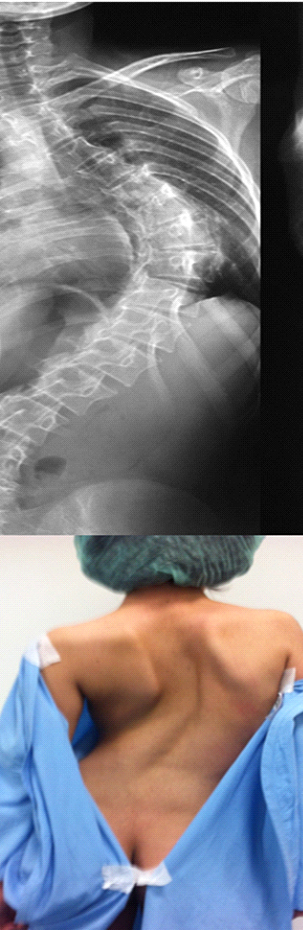

Сколіозом називають деформацію хребта в трьох площинах. Лікарі більше двох тисячоліть намагаються знайти спосіб лікування цього захворювання. На жаль, і досьогодні достеменно не відомі причини його виникнення.

Сколіоз нервово-м’язового типу виникає через аномалії розвитку хребта. Такий вид хвороби найбільш схильний до прогресування. При лікуванні цього захворювання лікувальна фізкультура не є ефективною, тому показане оперативне втручання. Те ж стосується і вродженого сколіозу.

Консервативно можна спробувати зупинити подальшу деформацію хребта, а усунути деформацію можна тільки хірургічно. Якщо йдеться про ідіопатичний сколіоз, то він, на жаль, зворотнього розвитку не має.